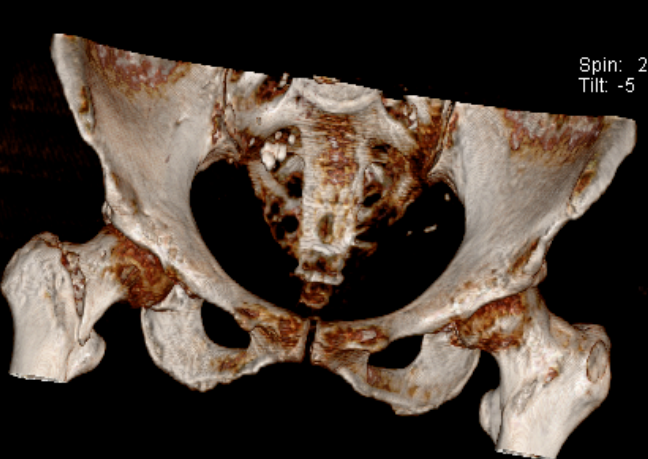

93 岁 的患者李奶奶和 91 岁 的患者蒋奶奶,都是在家不慎摔跤,急诊检查后发现为 股骨粗隆间骨折,进而入住我院骨科接受治疗。

我院多科室协同合作, 根据快速康复理念,经详细检查、排除禁忌症、与家属充分沟通后,成功为李奶奶、蒋奶奶实施 股骨粗隆间骨折闭合复位内固定术(PFNA),手术治疗效果良好。

髋部骨折,又称为股骨近端骨折,常见的是股骨粗隆间骨折、股骨颈骨折。